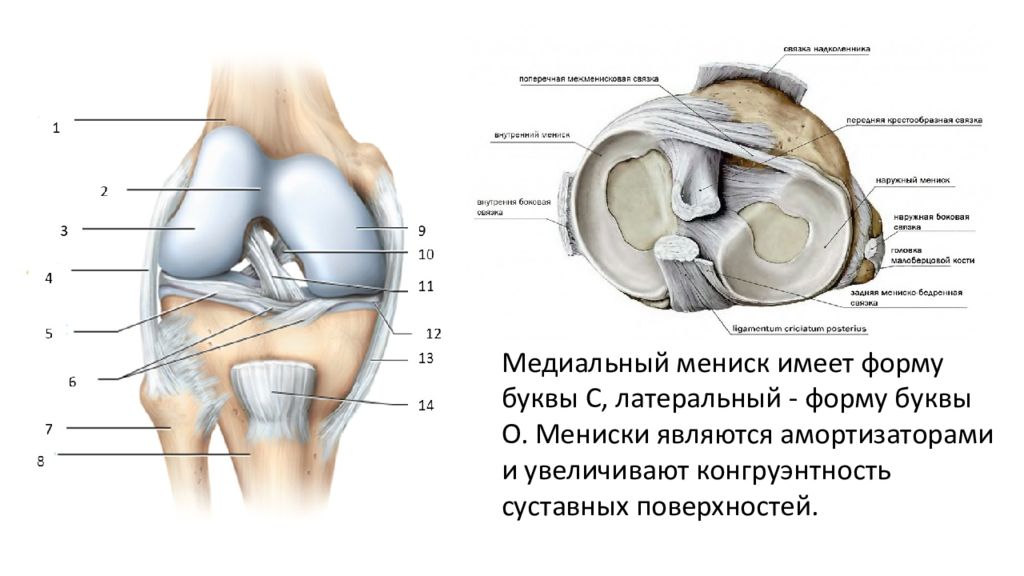

Анатомические изображения менисков и коленного сустава

Раздел: Иллюстрированные советы